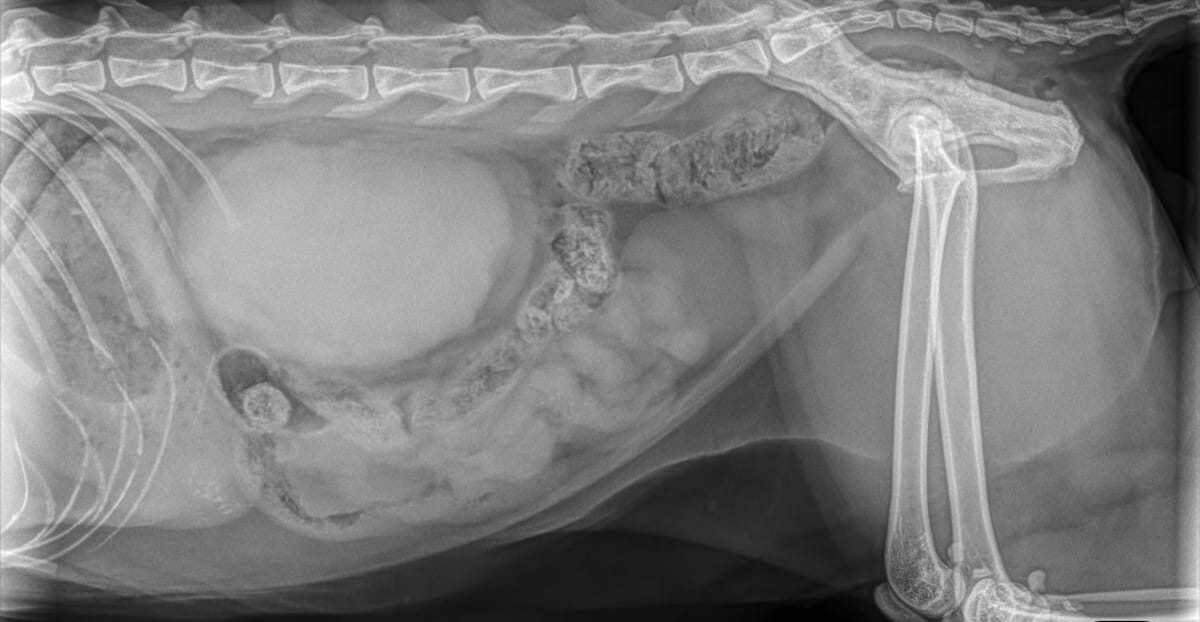

This week’s case is a 5-year-old male castrated Domestic Short Hair presenting for weight loss and anorexia. He was found to be 5% dehydrated and markedly azotemic.

5 yr DSH presenting for anorexia and weight loss and found to be markedly azotemic.

What is your primary differenital